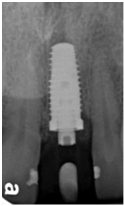

97/09/23 右下第一小臼齒植牙完成時

98/01/08經過三個半月做右下第一小臼齒的二階暴露,發覺鄰牙的植體高度竟已掉下來